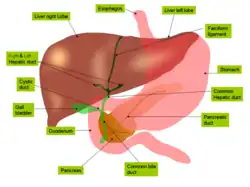

Anatomie

Le foie est un organe intrapéritonéal : il est recouvert à sa surface de péritoine viscéral, qui le rattache à la paroi abdominale en se réfléchissant sur le péritoine pariétal. La capsule de péritoine viscérale qui l'entoure est appelée la capsule de Läennec. Toutefois, elle possède une zone non péritonisée appelée l'area nuda, située en arrière et contre le diaphragme. De plus, le foie est entièrement recouvert d'une capsule fibreuse sous-jacente au péritoine viscéral, appelée la capsule de Glisson.

On distingue habituellement deux faces au foie :

- une face diaphragmatique, lisse et en forme de dôme qui épouse la concavité du diaphragme ;

- une face viscérale, plane et présentant de nombreux replis de péritoine et des fissures.

La face diaphragmatique est séparée de la face viscérale en avant par le bord inférieur, qui est aigu et dit « tranchant », en regard du rebord costal inférieur, et en arrière par le bord postérieur, qui est plus arrondi.

Le ligament falciforme, issu du mésentère ventral lors du développement embryonnaire, relie le foie à la paroi abdominale antérieure. C'est un repli de péritoine tendu verticalement depuis l'appendice xiphoïde et le diaphragme jusqu'à l'ombilic. Il contient entre ses deux feuillets le ligament rond du foie, vestige de la veine ombilicale qui s'oblitère après la naissance. Ce ligament falciforme est continu avec la capsule de Glisson qui entoure le foie : sur la face antéro-supérieure (face diaphragmatique), il sépare le foie en deux parties gauche et droite, souvent considérées comme des lobes droit et gauche du foie. Sur la face viscérale, le ligament falciforme se continue par la capsule, tandis que le ligament rond qu'il contient s'insère dans la moitié antérieure d'un sillon appelé le sillon sagittal gauche.

On distingue donc au foie deux lobes — gauche et droit — sur la face diaphragmatique du foie, marqué par l'insertion du ligament falciforme. Cette subdivision du foie repose uniquement sur un critère anatomique : on ne devrait pas parler de « lobe », car la lobulation d'une glande repose sur d'autres critères structuraux, notamment la présence de septa conjonctifs qui viennent séparer la glande en plusieurs unités fonctionnelles. Le lobe droit du foie est le plus volumineux, tandis que le lobe gauche est petit et se termine en pointe (apex du foie).

En plus de ces deux lobes principaux, on distingue deux petits lobes à la face viscérale du foie : le lobe caudé et le lobe carré.

Face diaphragmatique

La face diaphragmatique est lisse et convexe. Elle occupe les parties antéro-supérieure et postéro-supérieure du foie. Elle présente dans sa partie postérieure une zone à nu, non péritonisée, appelée l'area nuda, qui la fixe au diaphragme.

En avant, elle est séparée du diaphragme par le récessus subphrénique, une extension de la grande cavité péritonéale. Ce récessus subphrénique est séparé en deux par l'insertion du ligament falciforme à la paroi abdominale antérieure, sur le péritoine pariétal. Le foie est fixé en haut par les ligaments coronaires, qui sont des replis péritonéaux en continuité avec la capsule de Glisson, et donc en continuité avec les ligaments falciformes d'une certaine façon. On distingue deux lames à ces ligaments coronaires par rapport à la zone dépéritonisée qu'elles entourent : une lame antérieure, et une lame postérieure. Aux extrémités supérieures droite et gauche du foie, les deux lames s'adossent et forment les ligaments triangulaires droit et gauche du foie, respectivement.

Face viscérale

La face viscérale du foie occupe la partie inférieure du foie, dans le plan transversal, et regard en arrière, en bas et à gauche. Elle présente deux fissures sagittales et une fissure transversale qui lie ces dernières et forme un « H » :

- la fissure sagittale droite (ou sillon sagittal droit) correspond à la fosse de la vésicule biliaire en avant, et au sillon de la veine cave inférieur en arrière ;

- la fissure sagittale gauche (ou sillon sagittal gauche) est le sillon continu formé par la fissure du ligament rond en avant, et par la fissure du ligament veineux en arrière. Le ligament rond du foie est le reliquat fibreux de la veine ombilicale, qui transporte le sang bien oxygéné et riche en nutriments, du placenta au fœtus. Le ligament veineux est également un vestige, du conduit veineux, qui court-circuite la circulation hépatique et achemine ainsi les nutriments du placenta à la circulation systémique. Lors de la naissance, ces deux veines s’oblitèrent en tissu fibreux (ligaments) ;

- le sillon transversal relie en arrière les deux sillons sagittaux et forme le hile du foie (ou porte du foie), point de passage des vaisseaux vasculaires et lymphatiques, des nerfs et des conduits biliaires.

C'est donc par la face viscérale que rentrent et sortent des structures telles que des vaisseaux sanguins et lymphatiques, nerfs et conduits biliaires, au niveau de la porte du foie (hile hépatique) : la porte du foie sert de porte de rentrée pour l'artère hépatique propre, la veine porte hépatique et les lymphonoeuds hépatiques, et de point de sortie pour les conduits biliaires (conduit hépatique commun et cystique, formant le cholédoque à la sortie du hile).

La face viscérale présente deux petits lobes accessoires : le lobe carré et le lobe caudé.

Vascularisation

Les vaisseaux qui irriguent et drainent le foie sont regroupés en trois groupes[7] :

- les vaisseaux du pédicule hépatique (vaisseaux afférents), comprennent les artères hépatiques propres qui va donner l’artère hépatique droite et gauche, le système porte et le tronc hépatique provenant l’artère coronaire stomachique. Ils acheminent le sang artériel et veineux vers les sinusoïdes hépatiques ;

- les veines hépatiques (ou sus-hépatiques), qui drainent le sang et le ramènent dans le circuit systémique en s'abouchant dans la veine cave inférieure ;

- les vaisseaux accessoires, qui ont une origine variée et inconstante.

L'apport sanguin est réalisé par l'artère hépatique propre, amenant le sang oxygéné, et par la veine porte ramenant le sang du tube digestif, du pancréas et de la rate riche en nutriments en période postprandiale. Le sang de ces deux vaisseaux se mélange dans les sinusoïdes hépatiques qui cheminent entre les travées hépatocytes pour se réunir dans une veine centrolobulaire. En période post-prandiale, environ 70 % du sang est issu de la veine porte hépatique, et 30 % de l'artère hépatique propre. Le sang veineux porte est riche en nutriments, tandis que le sang artériel sert principalement à l'apport d'oxygène. La vascularisation hépatique est dite mixte. Le foie contient près de 13 % de la quantité de sang présent dans notre corps, avec une augmentation importante du volume la nuit, jusqu'à 40 %[1].

L'artère hépatique propre est la branche terminale de l'artère hépatique commune, issue du tronc cœliaque. L'artère hépatique commune donne sur son chemin les artères gastrique droite et gastroduodénale avant de devenir l'artère hépatique propre, qui remonte vers le hile hépatique (porte du foie). Une fois dans la porte du foie, l'artère hépatique propre bifurque en deux branches principales, les branches hépatiques droite et gauche, de la même manière que la veine porte hépatique se divise en deux branches droite et gauche.

Du fait de cette bifurcation des vaisseaux afférents, ainsi que des conduits biliaires, on divise arbitrairement le foie en deux compartiments lobaires : le foie droit et le foie gauche. Cette compartimentation repose sur des critères structurels et fonctionnels qui sont interne au foie. Sur le plan anatomique de surface, on divise habituellement le foie en deux lobes par l'insertion du ligament falciforme : les deux lobes « anatomiques » ne sont pas les mêmes que ceux qui viennent d'être cités. De plus, on peut considérer le lobe caudé du foie comme un troisième lobe fonctionnel, car il reçoit des artères et des veines des deux branches principales (veines et artères) caudées droite et gauche.

Le retour veineux du foie s'effectue par les veines hépatiques, également appelées veines sus-hépatiques, qui se jettent dans la veine cave inférieure. On distingue trois veines hépatiques : la veine hépatique droite, moyenne, et gauche.

Lobes du foie

Le foie est divisé en deux lobes séparés par le ligament falciforme (ou ligament suspenseur)[8], le lobe droit (deux tiers du volume du foie) et le lobe gauche (un tiers du volume). On peut également individualiser deux autres lobes mineurs en taille : le lobe caudé (ou lobe de Spiegel) et le lobe carré[9].

Le lobe caudé, également appelé lobe de Spiegel, est visible à la partie postérieure de la face viscérale du foie, et est limité sur sa gauche par le sillon du ligament veineux (sillon sagittal gauche), sur sa droite par le sillon de la veine cave inférieure (sillon sagittal droit) et finalement en avant par le hile du foie. Il est nommé ainsi car il est muni d'un prolongement allongé en forme de queue, le processus caudé, qui rejoint le processus papillaire (faisant également partie du lobe caudé). Sur le plan anatomique comme fonctionnel, il est considéré comme un lobe individuel : sur le plan anatomique, grâce aux limites citées précédemment, et sur le plan fonctionnel, par l'apport vasculaire. Il est vascularisé par des vaisseaux afférents venant des foies droit et gauche (veines et artères caudées gauches et droites).

Le lobe carré du foie est visible est à la partie antérieure de la face viscérale du foie. Il est limite sur la gauche par le sillon du ligament rond (partie antérieure du sillon sagittale gauche), à droite par le fond de la vésicule biliaire (fundus) et en arrière par le hile du foie.

Cette subdivision du foie en plusieurs lobes — deux lobes principaux et deux lobes accessoires — repose sur des critères anatomiques et ne correspondent pas aux critères de lobes d'une glande. Cette subdivision est donc purement obsolète, et les lobes anatomiques ne sont pas séparés par des septa conjonctifs entre deux.

Voies biliaires intra- et extrahépatiques

Les hépatocytes sécrètent la bile dans les canalicules biliaires. Ceux-ci sont formés par des invaginations de la membrane plasmique des hépatocytes et forment en fait un espace virtuel. Les canalicules de chaque hépatocyte se déversent dans un canal biliaire primitif appelé canal de Hering. Par la suite, la bile poursuit son parcours dans des canaux biliaires interlobulaires lesquels sont constitués de cellules biliaires (cholangiocytes) qui reposent sur une lame basale. Les canaux interlobulaires forment ensuite des canaux biliaires de plus gros calibre et finissent par former les canaux hépatiques droit et gauche dont la réunion forme le canal hépatique commun qui quitte le foie au niveau du hile hépatique. Le canal cystique issu de la vésicule biliaire se jette dans le canal hépatique commun qui devient le cholédoque, lequel s'abouche dans le duodénum.